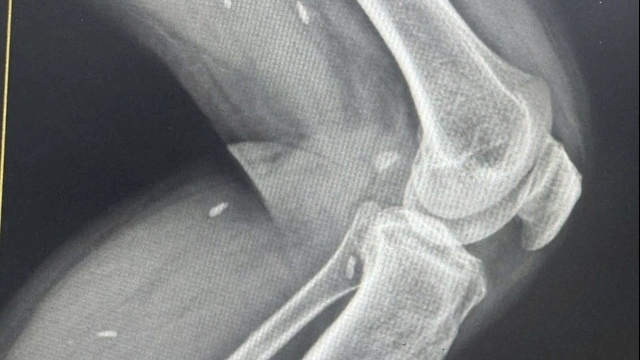

Nhiều BV tự chủ chỉ định các xét nghiệm cận lâm sàng được cho là “quá tay” - Ảnh: Duy Tính